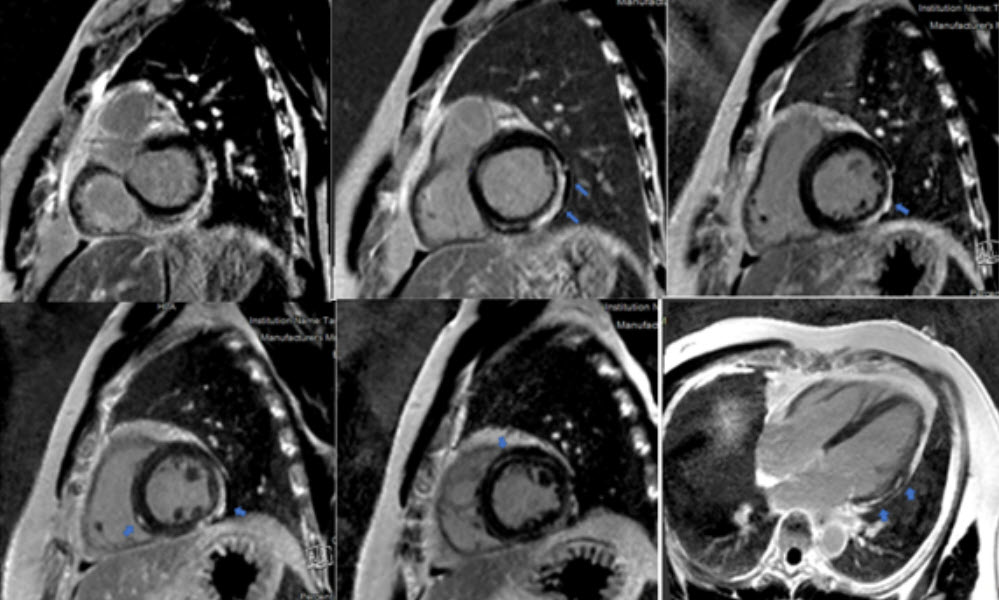

Chụp cộng hưởng từ tim (MRI) giúp phát hiện vùng viêm, phù hoặc hoại tử cơ tim — phương pháp không xâm lấn nhưng rất giá trị trong đánh giá mức độ tổn thương.

Hình ảnh MRI tim cho thấy vùng cơ tim bị viêm và tổn thương do phản ứng miễn dịch.